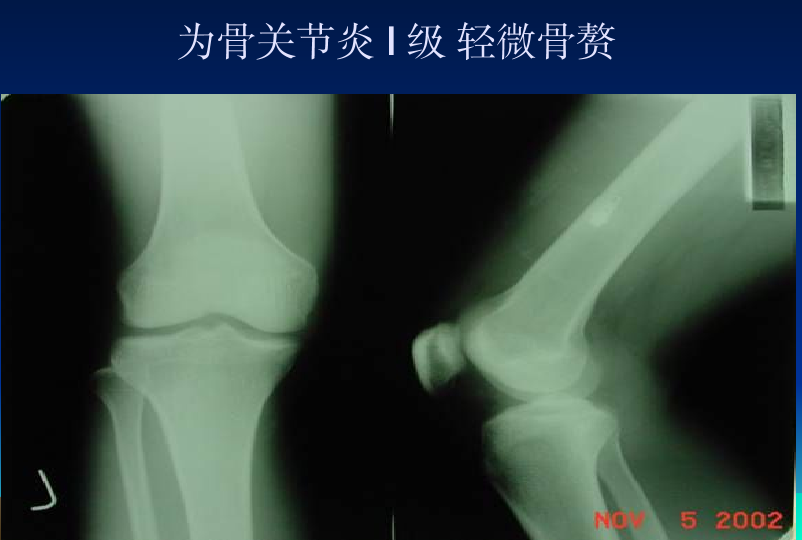

浅谈膝关节炎诊疗体会